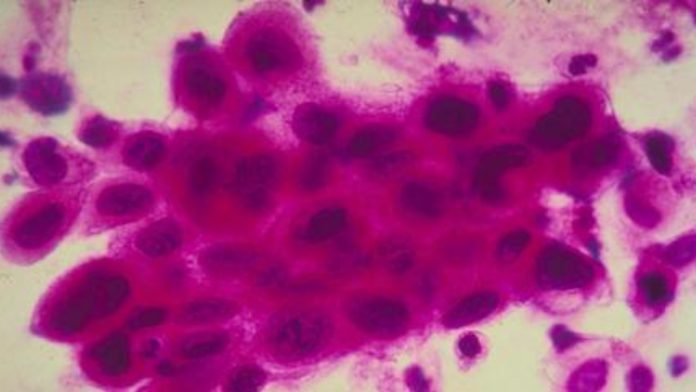

O tratamento de alguns tipos de câncer, desenvolvido pelo Instituto Butantan, Universidade de São Paulo (USP) e Hemocentro de Ribeirão Preto, tem apresentado bons resultados e sua utilização no Sistema Único de Saúde (SUS) vem sendo estudada. Chamado de terapia celular CAR-T Cell, o procedimento já é adotado nos Estados Unidos e em outros países para tratar linfomas e leucemias avançadas, como último recurso.Veja também:Ophir Loyola orienta para a detecção do câncer cerebral Alerta: confira sinais do câncer de intestino Nessa forma de tratamento, as células T do paciente (um tipo de célula do sistema imunológico) são alteradas em laboratório para reconhecer e atacar as células cancerígenas ou tumorais. O termo CAR refere-se a um receptor de antígeno quimérico (chimeric antigen receptor, em inglês).“O T vem de linfócitos T, que são células do sangue responsáveis pelo combate a infecções e a alguns tipos de câncer”, explica o professor de hematologia, hemoterapia e terapia celular da Faculdade de Medicina da Universidade de São Paulo (USP) Vanderson Rocha, também coordenador nacional de terapia celular da rede D’Or.O câncer é muito ‘esperto’, afirma Rocha. “As células T ‘fogem’ um pouco do reconhecimento das células do câncer. No tratamento, nós retiramos essas células do paciente, através do sangue, e as colocamos em laboratório, para serem modificadas geneticamente, para ‘armá-las’ contra as células do câncer.”No programa de tratamento, um dos pacientes estava com linfoma não-Hodgkin. “Cerca de um mês após a produção dessas células, podemos infundi-las no sangue. Então, as células vão se direcionar contra as células do tumor, porque estão capacitadas a fazer isso, para poder combater os tumores, no caso desse paciente, o linfoma. Ele teve uma remissão completa um mês depois da injeção dessas células”, acrescenta o especialista.Como a terapia celular ainda está em fase experimental no Brasil, os pacientes foram tratados até agora de forma compassiva, ou seja, por decisão médica, quando o câncer está em estágio avançado e não há alternativas de terapia.Os pacientes começaram o tratamento no Hospital das Clínicas da Faculdade de Medicina de Ribeirão Preto, no interior paulista, em 2019. Nos Estados Unidos, o FDA (agência reguladora de saúde do país) fez a liberação para uso da indústria farmacêutica em 2017.No Brasil, o uso da indústria farmacêutica começou em janeiro deste ano. Para quem pode pagar o tratamento, o custo é de cerca de R$ 2 milhões. O desafio brasileiro é tornar a terapia acessível em larga escala por meio da saúde pública, mas ainda há um caminho a percorrer para que esteja disponível gratuitamente.“As células são retiradas, enviadas para os Estados Unidos e voltam para os pacientes. No caso específico do grupo de estudos, toda essa produção foi feita no Brasil, por meio de pesquisa e ciência, pela Fapesp [Fundação de Amparo à Pesquisa do Estado de São Paulo], pelo CNPq [Conselho Nacional de Desenvolvimento Científico e Tecnológico], pelo Instituto Butantã, pela Fundação Hemocentro, Faculdade de Medicina da USP, na capital e em Ribeirão Preto. Foi toda uma equipe de cientistas que permitiu a fabricação dessas células”, ressalta Rocha.O primeiro caso de remissão da doença por meio dessa técnica no país ocorreu em 2019, mas o paciente morreu por outra causa dois meses depois do tratamento. “O paciente obteve uma remissão parcial, mas pode ser que, naquele momento, ainda tivesse tempo de responder [totalmente ao tratamento]”, detalha o médico.Em 2019, a reportagem da Agência Brasil contou a história do aposentado Vamberto Castro, que, aos 62 anos, estava com linfoma em estado grave e sem resposta a tratamentos convencionais. Cerca de 20 dias após o início do tratamento, a resposta de saúde do paciente foi promissora: os exames passaram a mostrar que as células cancerígenas desapareceram. No fim do mesmo ano, no entanto, Vamberto morreu em decorrência de um acidente doméstico, não relacionado à doença. Em 2022, o governo de São Paulo ampliou a capacidade do programa. Dois centros de saúde, um na capital paulista e um em Ribeirão Preto, têm produzido, desde então, compostos para a terapia celular CAR-T. A capacidade inicial de tratamento será de até 300 pacientes por ano. O programa faz parte de um acordo de cooperação entre o Instituto Butantan, a USP e o Hemocentro de Ribeirão Preto.Resposta imediataAté o momento, 14 pacientes foram tratados com o CAR-T Cell com verbas da Fapesp e do CNPq. Todos os pacientes tiveram remissão de pelo menos 60% dos tumores. A recuperação foi na rede SUS. “As respostas que estamos tendo aqui, é claro que em um número pequeno de pacientes, são muito semelhantes às que temos fora do Brasil. Isso é muito importante”, observa Rocha.Para um desses pacientes, Paulo Peregrino, a resposta foi imediata, conta o professor de hematologia. “Nesse caso, o que impressiona é a resposta imediata de um paciente que tinha muitos tumores. Então, as imagens [pet scan do corpo do paciente] mostram: tudo que é preto [os tumores] desaparecem completamente em um mês. Repetimos recentemente as imagens, e continua tudo em remissão. Quer dizer, ele está livre do tumor neste momento. Porém, para falar de cura, demora alguns anos, porque, mDiante da notícia da remissão completa do câncer, Peregrino se disse surpreso. “Primeiro, não acreditei que estava daquele jeito, não conhecia aquela imagem [pet scan], não sabia que havia chegado naquele ponto e, ainda, depois que chegou aquele ponto [de remissão], depois do Car T Cell”.Para ele, a disposição de participar do estudo não foi apenas pela possibilidade de cura. “Quando decidi pelo Car T Cell, eu sabia que era um estudo compassivo, que poderia ser usado — e deve ser usado — para que outras pessoas no futuro possam ter um tratamento com mais qualidade de vida. Isso, para mim, era um dos objetivos desde o início. Na hora em que me predisponho a fazer parte do estudo e deixar alguma coisa de conhecimento que possa ajudar os outros no futuro, estou fazendo o bem”, diz o publicitário, que tem 61 anos.Paulo estava tratando de câncer há 13 anos. Primeiro, foi um câncer de próstata, em 2010, que ele tratou até 2014. Depois, em 2018, descobriu o linfoma não-Hodgkin, lembra o professor. “Passou por seis ciclos de quimioterapia, mas a doença voltou depois de alguns anos, então ele fez transplante de medula autólogo. Porém, no Paulo, a doença voltou após o transplante, aí não havia mais possibilidade terapêutica, e o câncer foi aumentando. Conseguimos infundir a célula T, e ele teve essa resposta maravilhosa, já está de alta.” No domingo (28), Paulo teve saiu hospitalar e se recupera em casa.O médico diz que foi emocionante ver a resposta do paciente. “É um tratamento desenvolvido no Brasil, relativamente recente, e tivemos experiência com outros casos, mas este realmente impressionou a todos. A equipe ficou surpresa com a resposta desse paciente, a quem não teríamos muito mais para oferecer e que iria para os cuidados paliativos”, admite Rocha. Reações adversasA terapia tem se mostrado eficaz, mas, como a maioria dos tratamentos de saúde complexos, apresenta reações adversas. Na ‘guerra’ entre as células T alteradas em laboratório e o câncer, o corpo se inflama com os ‘destroços’ dos cânceres, e o paciente muitas vezes precisa ser monitorado em unidade de terapia intensiva (UTI), explica Rocha. “O paciente, após a infusão das células, vai ter uma reação, uma inflamação importante destas. Cinquenta por cento dos pacientes que recebem essas células vão ser tratados na UTI, porque têm que ser monitorizados, tomar anti-inflamatórios e corticoides.Existe ainda a síndrome de neurotoxicidade imunológica, no qual o paciente pode ter problemas neurológicos, como dificuldade de escrever e de andar. “Isso tudo passa com o tempo, mas são reações importantes e adversas.”De acordo com Rocha, os efeitos colaterais podem inclusive levar pacientes à morte. “Porém, como adquirimos mais experiência em tratar esse tipo de síndrome, têm melhorado muito os resultados da chamada síndrome de liberação de citocinas, que ocorre em processos graves e inflamatórios. Há também a deficiência imune: os pacientes que recebem as células CAR-T durante muito tempo vão receber medicamentos para melhorar a imunidade.”ExpectativasSegundo Rocha, ainda falta verba para a ciência e a pesquisa para que a terapia seja disponibilizada em grande escala. “Custa muito caro produzir essas células, e faltam ainda os estudos de fases 1 e 2, que vão começar no próximo mês, para demonstrar que funciona, que não tem toxicidade maior para os pacientes e que pode estar no serviço público. Mas é uma etapa que demora ainda alguns anos, por isso, é importante investir em pesquisa.”O especialista destaca que existe ainda possibilidade de uso da técnica em caso de tumores sólidos. “O grande problema é que as células T não conseguem [se] infiltrar no tumor. Então, uma das possibilidades é encontrar outros tipos de células que possam penetrar o tumor e, para isso, precisamos de verba e apoio para a comunidade científica.”AnvisaEm nota, a Agência Nacional de Vigilância Sanitária (Anvisa) informa que o procedimento de obtenção do produto à base de células CAR-T, utilizado no paciente Paulo Peregrino, foi notificado em janeiro deste ano e avaliado com prioridade, favorecendo a pesquisa científica e o uso experimental para o tratamento do linfoma.“A Agência ressalta que essa não é uma terapia de rotina e não se aplica a todo tipo de câncer, e que estudos adicionais precisam ser conduzidos”, diz a nota.A agência reguladora acrescenta que está empenhada na avaliação de novas terapias avançadas e que recentemente selecionou dois projetos, por meio de um edital de chamamento, com o objetivo de apoiar a aprovação de ensaios clínicos e a produção da promissora terapia no Brasil.“O Hemocentro de Ribeirão Preto tem conduzido a administração do produto em um contexto experimental, fora da estrutura de um ensaio clínico controlado. Esse recurso é aplicável em circunstâncias onde há risco imediato à vida do paciente ou quando se trata de doenças para as quais não existem alternativas terapêuticas disponíveis no país. O uso experimental deve ser notificado à Agência, conforme previsto em seu regulamento técnico (RDC 505/2022)”, completa a nota.Projeto pilotoA Anvisa informa que tem um projeto piloto de cooperação técnica regulatória para o desenvolvimento de produtos de terapia avançada (PTAs) de interesse do SUS. O Instituto Butantan e o Hemocentro de Ribeirão Preto foram aprovados pelo edital de chamamento, que tem como objetivo selecionar desenvolvedores nacionais para participar da iniciativa.O objetivo do projeto é estabelecer um modelo de cooperação regulatória dinâmico e eficaz. “Tal cooperação envolverá a Anvisa, os pesquisadores e desenvolvedores brasileiros e o setor produtivo de saúde nacional. Este esforço colaborativo tem como meta estimular o desenvolvimento de PTAs para uso no SUS, abordando a demanda de um número cada vez maior de pacientes com uma grande variedade de doenças sem alternativas terapêuticas adequadas. Essas doenças incluem distúrbios genéticos raros, doenças autoimunes e oncológicas”, destaca a agência.O princípio do projeto piloto é buscar estratégias para alcançar elevados padrões de segurança, eficácia e qualidade dos produtos em estudo, para satisfazer as necessidades dos pacientes brasileiros de maneira oportuna, impulsionando o desenvolvimento e a aprovação dessas terapias avançadas de forma ágil, informa a agência.Apesar de os desenvolvedores já terem iniciado as interações com a agência, os protocolos pré-clínicos e clínicos do produto em questão ainda estão em fase de ajustes, diz a Anvisa. Em março de 2023, após a submissão da documentação inicial para o estudo, a Anvisa pediu mais esclarecimentos sobre requisitos específicos de ensaios pré-clínicos de segurança, questões relacionadas ao ensaio clínico proposto e avaliações de segurança necessárias.“Deve-se ressaltar também que a documentação relacionada à fabricação do produto e aos respectivos controles está sendo elaborada e ainda não foi submetida à Agência para análise”, acrescenta.Assim, somente após receber respostas aos questionamentos feitos e a documentação relativa à produção da terapia, a Anvisa poderá se pronunciar sobre a aprovação do ensaio clínico proposto. Vale salientar que o projeto já foi classificado como prioritário para análise pela agência”, conclui a nota.